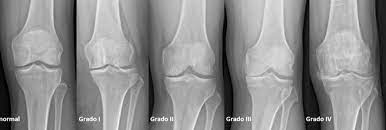

Antidepresivos para la artrosis de cadera y rodilla

Hay evidencia de certeza alta de que el uso de antidepresivos para la artrosis de rodilla produce una mejoría insignificante desde el punto de vista clínico en el dolor medio y la funcionalidad. Sin embargo, un pequeño número de personas tendrá una mejoría importante del 50% o más en el dolor y la funcionalidad. Este hallazgo fue consistente en todos los ensayos. El dolor en la artrosis se podría deber a diversas causas que difieren entre las personas. Es posible que la causa del dolor que responde a este tratamiento solo esté presente en un pequeño número de personas. Hay evidencia de certeza moderada de que los antidepresivos tienen un pequeño efecto positivo sobre la calidad de vida, con heterogeneidad entre los ensayos. Cochrane Database of Systematic Reviews 21 de octubre de 2022